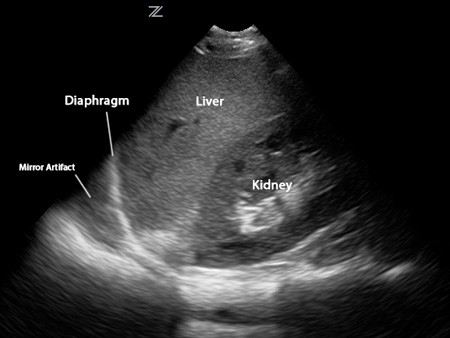

Written by Judy Gichoya and Alexandre Cadrin-Chênevert recenty directed a post to us from one of the fast.ai student asking about housefield units conversion for MRI. Jeremy Howard Question This post summarizes an overview of the physics of image formation for MRI and CT scans to help understand the concept of intensities and mapping For the impatient reader, answered this question Alexandre Cadrin-Chênevert If this of interest then read on…. What is a modality ? Radiology relies on various types of cameras (or ) — that work differently to capture images from patients. These include ultrasound , Computed Tomography (CT scan), Magnetic Resonance Imaging (MRI), PET/CT , and plain Xray. Yes, think of the various modalities related to the different camera types for medical imaging. In the picture below, you can see the appearance of the liver across different cameras (modalities) modalities Liver images aquired through ultrasound Images of the liver / upper abdomen acquired from an MRI CT scan images of the upper abdomen including liver How are MRI images formed? MRI physics can be summarized as . signal generation , image formation and sequences A: Signal Generation Our bodies are made largely of water (72% of our bodies are made up of water). Water is composed of 2 Hydrogen molecules and 1 oxygen molecule (H20). This translates to a large amount of hydrogen molecules in our bodies. Hydrogen is a chemical element with an atomic number 1 (H+). Water composition in the human body The MRI machine is a big strong magnet (and the unit Tesla is used to signify the strength of the main magnet). When you are sitting at the core of the MRI machine for example for a Head MRI , then most of the hydrogen atoms in your body align to the direction of the main magnet (b0). This is called longitudinal magnetizaton. At rest, all your hydrogen atoms are spinning on their axis — Watch the video tagged below to learn about precession Since we know the main magnet strength (B0), then we can calculate Lamor frequency which can be used to generate signal to the hydrogen atoms that in precession. lamor frequency In the figure above, the H+ are at a precession frequency of 64 MHz evenly distributed across the magnetic field. The knowledge of the precession frequencies allows us to focus on a section of the body eg abdomen by shifting the magnetic field so we can apply a signal to a specific group of atoms rotating at a predetermined frequency. In addition to the main magnetic field, the MR machine has a radiofrequency (RF) signal that is applied perpedicular (90 degrees) to the main magnet and flips the hydrogen atoms to 90 degrees relative to the main magnet. I like to think of this as the process of tuning in to the radio where you are always looking for a specific frequency. This is called . The hydrogen atoms continue their precession, but also lose energy to go to a lower energy state (in the direction of the main magnet). transverse magnetization The above steps are summarized below …. Recap of signal generation As the hydrogen atoms lose energy to align themseves to the direction of the main magnet ( ), the signal they generate can be captured and plotted as a curve shown below. This curve is used to determine the — longitudinal relaxation T1 time T — T1 time which is the time require for protons to recover 63% of their longitudinal magnetization. T1 — time required for protons to recover 63% of their longitudinal magnetization Different body tissues will have different T1 times , and hence when you look at an MRI , you can identify fat (short T1) versus CSF. Difference in T1 curves across various tissues Another phenomenon that is occuring after the 90 degrees RF is summarized below. The hydrogen atoms are in phase at the beginning of the 90 degree RF pulse, but they undergo a spin -lattice interaction and get out of phase. If you plot this curve of , then you get a free induction decay T2* curve. T2 * curve T T2 time — is the time required for protons to lose 63% of their transverse magnetization. Now that we have explained T1 and T2 signals, we will move on to an example of meningioma to help understand the MR signals. Please note physics MR is a wide topic and we have not described concepts like diffusion , echo, gradient and TOF sequences,as well as artifacts . works by shifting the T1 curve to the left (shortens the T1 curve). Contrast Meningioma on MR In the above image, the left image is and the meningioma is difficult to identify. After administration of IV contrast (gadolinium), the T1 curve of meningioma shifts to the left and is seen as an enhancing lesion on the right image. T1 weighted image, CT physics — Hounsfield units (HU) CT images are not developed based on the hydrogen magic for MR. Instead , they use Xrays, a form of radiation focussed on part of the body being imaged. Different parts of the body (weaken) the Xray beam at different rates. Therefore to standardize the different values of attenuation, the is used to measure how easily a beam penetrates a a material. Since we know the attenuation of water to be zero, then the HU is calculated relative to water. attenuate attenuation coefficient HU calculation Therefore by measuring a region of interest, you can calculate the HU of a lesion and determine what it is — for example a fat containing lesion or a fluid containing lesion as a cyst. http://www.odec.ca/projects/2007/kimj7j2/index_files/Page1674.htm Tying it together (Deep Learning) Image segmentation is the process of drawing contours of an object to delineate its boundaries. In medical imaging, segmentation allows surface or volumetric quantification of a lesion or an anatomic structure. To train this kind of model, you need to show multiple images iteratively to the model with the associated segmented areas, often drawn manually by radiologists. U-Net is a specialized deep learning model architecture that allows automatic segmentation. U-Net: Convolutional Networks for Biomedical Image Segmentation From : U-Net: Convolutional Networks for Biomedical Image Segmentation ( ) https://arxiv.org/pdf/1505.04597.pdf U-net is designed intrinsically to perform very well with a small number of training cases. The architecture progressively encodes the initial image in a numerically squeezed representation, literally at the bottom of the U. Then, this bottom representation is decoded symmetrically to generate the automatic segmented area, also defined as a mask, as the final output. The training is optimized to minimize the difference between the proposed segmented area with the manually segmented ground-truth area. This property that allows an efficient training with a very small number of cases is particularly useful in medical imaging where expert manual segmentation is very costly. For meningioma segmentation, this technique could intuitively be tried on a post-gadolinium MRI sequence which is the sequence with the according to this pathology (i.e. meningiomas typically show avid enhancement, and bright signal, relative to the background). highest signal to noise ratio Hopefully this clarifies the idea of signals across CT and MR and helps you on your deep learning path. Consider joining our community that intersects radiology and imaging sciences with deep learning scientists here : . https://tribe.radai.club We discuss deep learning on our monthly journal club archived here : . Our next journal club is on 22nd February , 8 pm EST with a presentation from on — https://youtu.be/xoUpKjxbeC0 Timnit Gebru “Using deep learning and Google Street View to estimate the demographic makeup of neighborhoods across the United States” https://register.gotowebinar.com/register/8696551324404512003 Say thanks and references Numerous images of physics lecture were obtained from one of my best teachers at — Indiana University Radiology Department Dr. Isaac Wu Read more about MR physics here — MRI made easy